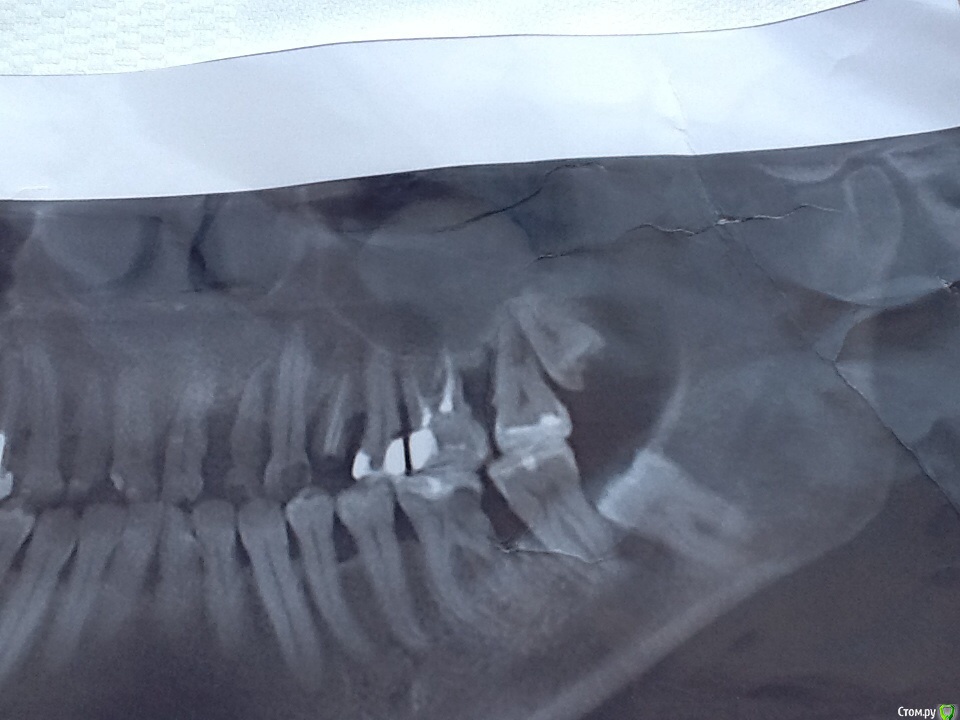

NoSpane Опубликовано 27 марта, 2017 Поделиться Опубликовано 27 марта, 2017 Добрый день, уважаемые доктора! Нужен ваш профессиональный совет касательно удаления всех ( ?! ) зубов мудрости и проблем с оставшимися жевательными зубами. Прокомментируйте, пожалуйста, весь снимок - что и как нужно делать! Хотелось бы сохранить хотя бы нижние " семерки" , но местные стоматологи соглашаются только на вариант удаление 7,8 в паре либо просто не берутся . По поводу верхней челюсти тоже разноречивые мнения - парно удалять, либо вначале 7, потом 8. В случае перфорации пазухи тоже разделились во мнениях- КАК ушивать и ушивать ли вообще Удалять по частям не хотят, предлагают целиком дергать Хотя сразу же мельком обмолвились, что не гарантируют сохранность челюсти при таком удалении Ходила-ходила по врачам, только время потеряла - в итоге полная неразбериха в голове Одинаковых мнений у врачей нет и какому специалисту довериться я не знаю Помогите, пожалуйста, определиться!!! Буду благодарна за любое мнение! Ссылка на комментарий

NoSpane Опубликовано 29 марта, 2017 Автор Поделиться Опубликовано 29 марта, 2017 Странно, зубные отложения ( поддесневые) уже снимали .Снимок сделан после снятия камней Я интересовалась , как проверить не остались ли камушки после чистки Врач ответил, что по снимку это невозможно определить Десны сильно кровят, даА в районе нижней правой пятерки десна синюшная и сам зуб шатается Укрепить как- нибудь подвижный зуб возможно? Шина ? Ссылка на комментарий

NoSpane Опубликовано 4 апреля, 2017 Автор Поделиться Опубликовано 4 апреля, 2017 Уважаемая St, можно задам последний вопрос? Наверху слева между 1 и 2 большой промежуток, зубы как то быстро разъехались Что можно предпринять в таком случае - как вернуть 2ку на законное место?! Над двойкой десна воспалена и "болит кость" ( по ощущениям) Ссылка на комментарий

St. Опубликовано 4 апреля, 2017 Поделиться Опубликовано 4 апреля, 2017 Зубы разьехались потому что кость ушла от воспаления, обратно она уже не выростет. Ссылка на комментарий